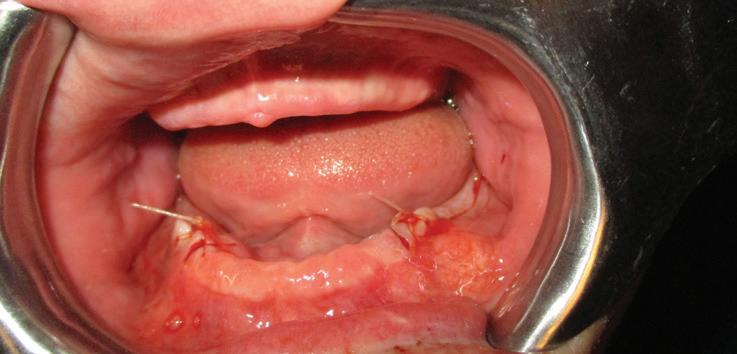

Implants were placed in areas of nos. 22 and 27. Implant no. 22 was Nobel Replace RP 4.3x11.5 torqued to 42.1 N/cm; implant no. 27 was Nobel Replace RP 4.3x11.5 torqued to 45.0 N/cm. Due to the patient wearing dentures, cover screws were placed and horizontal mattress sutures were placed. (The ends were clipped after the photos.) The patient was seen two days after and was healing well He was very happy with his treatment.